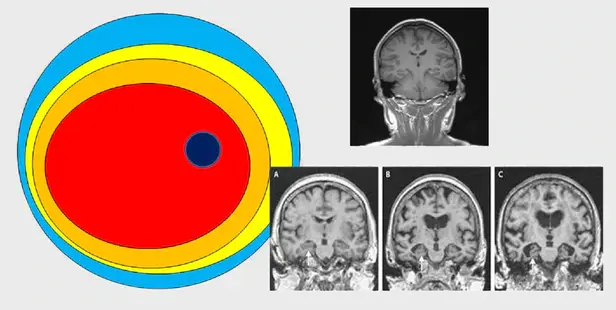

A-B 주관적인지장애를 겪는 사람의 뇌 상태. 촬영 사진만 보면 정상 뇌와 거의 차이가 없다. 그러나 이후 경도인지장애와 치매로 진행되면서 뇌의 모습이 확연히 변한다.

B-C 경도인지장애

C 치매의 뇌 상태

“몇가지 이유가 있다. 첫째, 너무 늦게 발견된다. 현대 의학은 객관적 근거가 있어야 병으로 진단한다. 예를 들어 MRI(자기공명영상)나 인지기능 검사를 통해 이상이 발견되어야 치매로 진단한다. 그러나 이런 방식으로 치매가 발견되었을 때에는, 대표적인 치매인 알츠하이머의 경우를 예로 들어 말하자면 알츠하이머치매 진행 7단계 중 4단계로 진행된 상태이다. 치매라고 진단을 받으면 많은 뇌세포가 이미 죽었거나, 제 기능을 못하는 좀비 상태이다. 더구나 MRI 촬영을 하면 죽은 세포 집단은 위축된 상태로 화면에 나타나지만 좀비세포 집단은 정상세포 집단과 구별이 잘 되지 않는다. 그래서 치매의 진단이 어렵다.